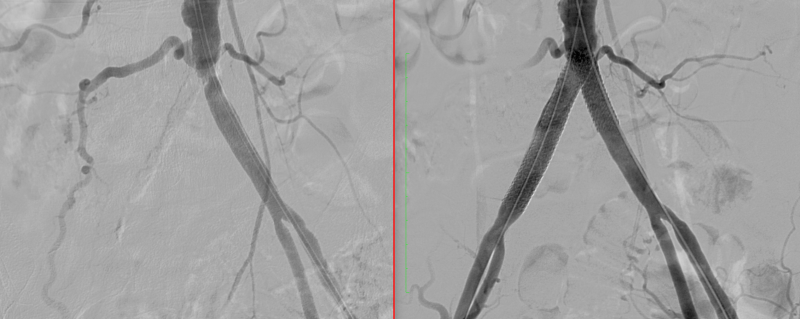

Αγγειοπλαστική λαγόνιων αρτηριών - kissing stents

Απόφραξη ΔΕ λαγονίου αρτηρίας και στένωση αριστερής - Αγγειοπλαστική με kissing stents